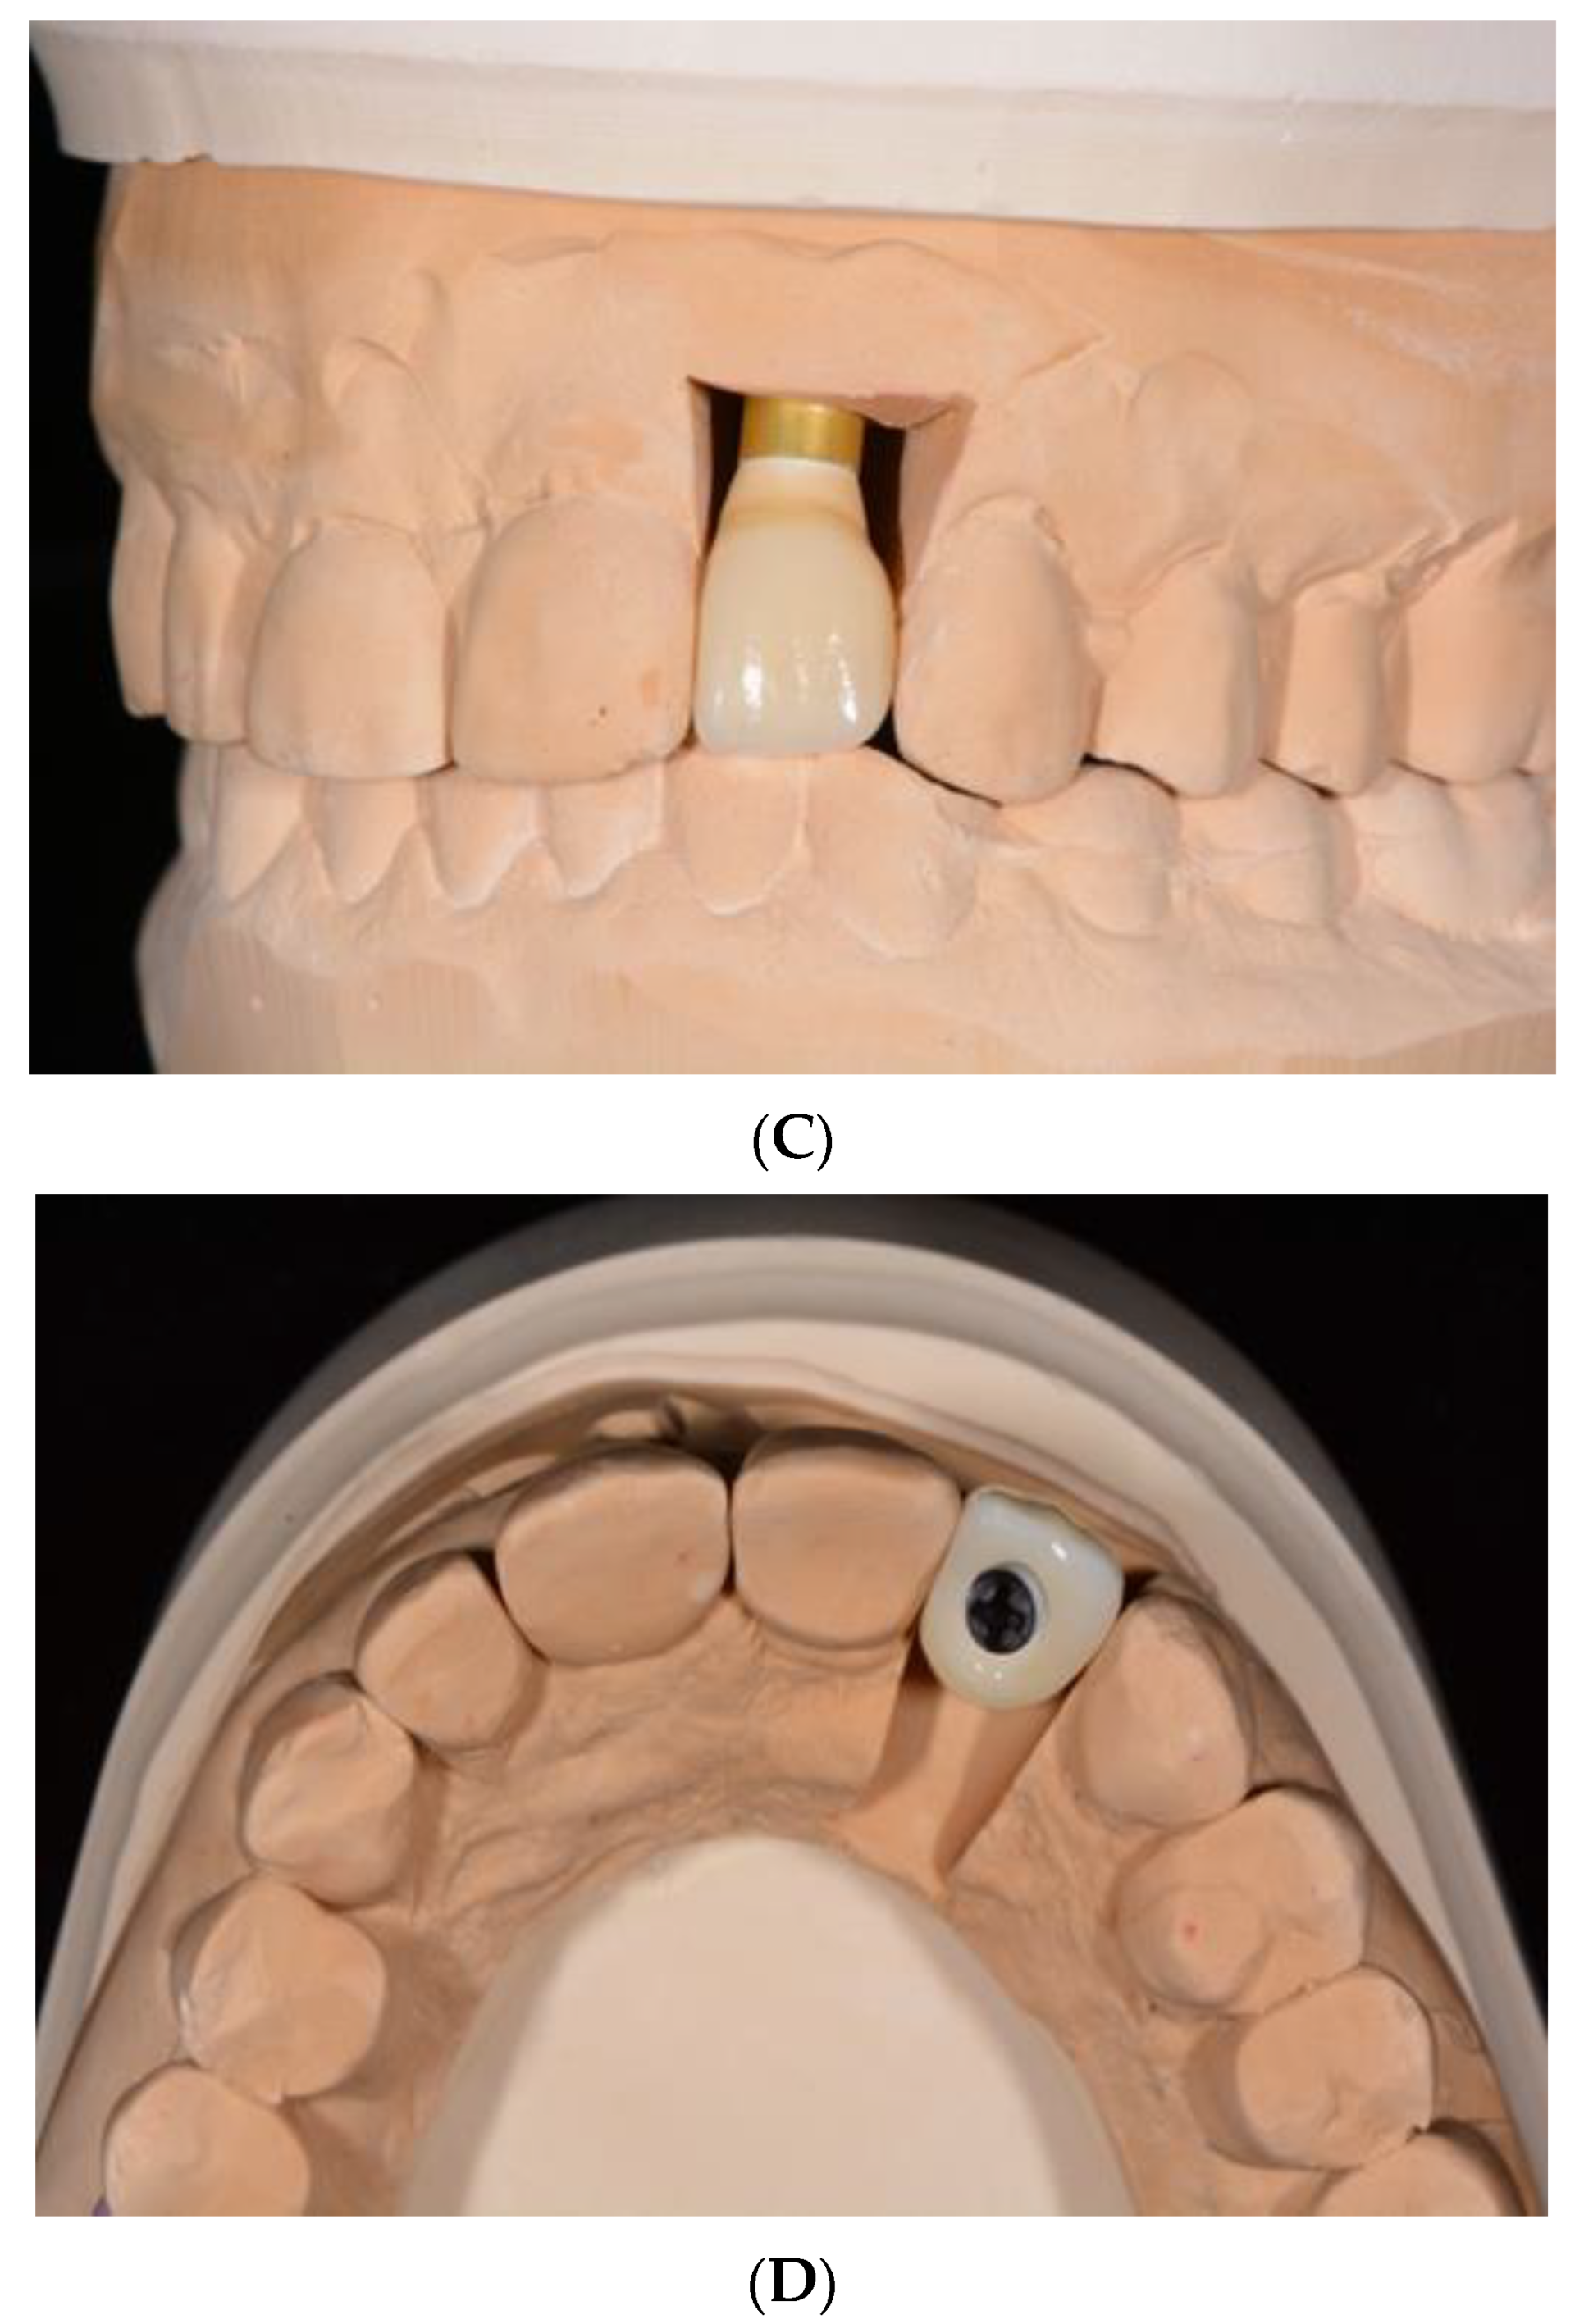

8. Custom-Made Root-Analogue Zirconia Implants

- Pessanha-Andrade, M.; Sordi, M.B.; Henriques, B.; Silva, F.S.; Teughels, W.; Souza, J.C.M. Custom-made root-analogue zirconia implants: A scoping review on mechanical and biological benefits. J. Biomed. Mater. Res. B Appl. Biomater. 2018, 106, 2888–2900. [Google Scholar] [CrossRef]

- Van Dooren, E.; Calamita, M.; Calgaro, M.; Coachman, C.; Ferencz, J.L.; Pinho, C.; Silva, N.R. Mechanical, biological and clinical aspects of zirconia implants. Eur. J. Esthet. Dent. 2012, 7, 396–417. [Google Scholar] [PubMed]

- Regish, K.M.; Sharma, D.; Prithviraj, D.R. An overview of immediate root analogue zirconia implants. J. Oral Implantol. 2013, 39, 225–233. [Google Scholar] [CrossRef] [PubMed]